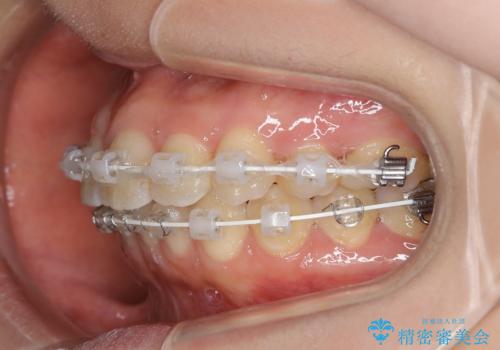

- 矯正装置

- 審美装置

- 抜歯矯正後の後戻りで前歯ガタつきが主訴で来院された患者様です。

後戻り矯正や非抜歯矯正はインビザラインをご案内する事が多いですが、自己管理の煩わしさから、目立たないワイヤー装置にて矯正治療を行うこととしました。

後戻りの程度としては軽度なので、治療期間としては短く終えることが出来ました。

前歯の正中線も改善され大変満足して頂きました。